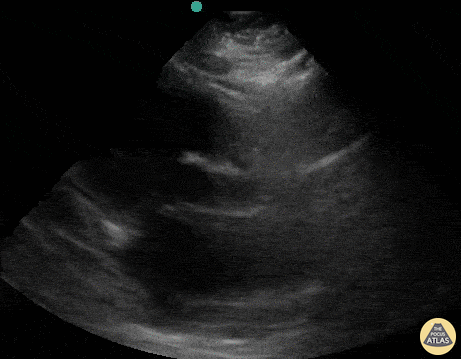

A patient presented with out-of-hospital cardiac arrest. POCUS was used to confirm presence of cardiac standstill. Note the absence of movement of the left ventricular free wall. Melissa Myers, MD. Emergency Medicine in Texas. Ultrasound Fellowship Program Director. @melissamyersmd